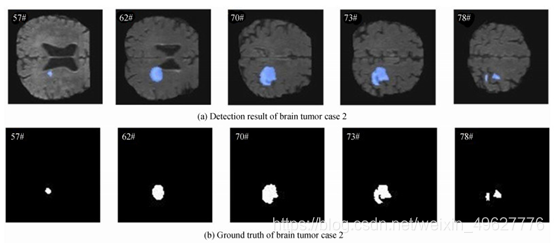

从脑肿瘤测试集中任选3个病例样本进行检测结果可视化分析,图 17~19分别为3个病例中5个序列的检测结果,以及对应序列的脑肿瘤病灶金标准图.

图 18 脑肿瘤病例2结果图

从图 17~19可以看出,设计的多模态脑肿瘤病灶检测方法所得到的检测结果,与金标准拟合程度高,说明该方法可有效检测出MRI脑部影像中脑肿瘤病灶.